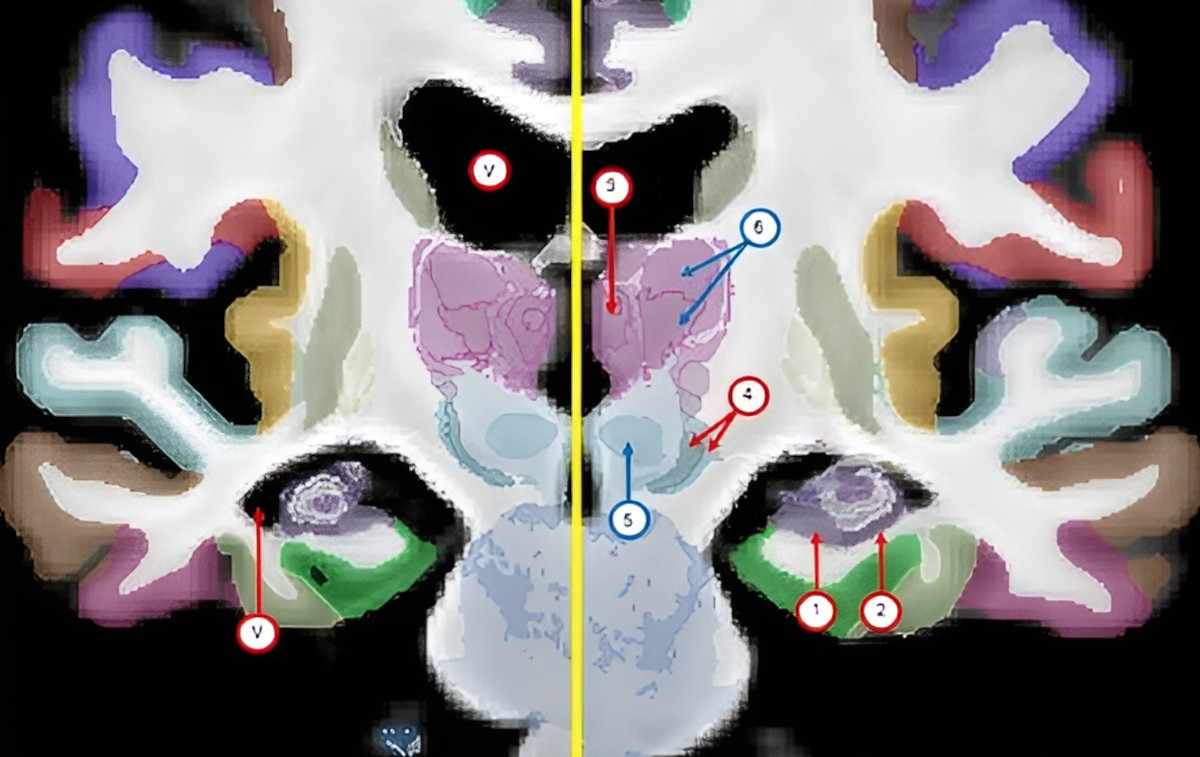

The atlas, called NextBrain, took the research team six years to build through a painstaking process using post-mortem tissue from five human brains. Each brain was dissected and sectioned into 10,000 pieces, stained to help identify brain structures, photographed under a microscope, and then reassembled into a 3D digital model.

AI was used to help align the microscope images and the MRI scans, accounting for the differences between the two techniques and ensuring that the pieces did not overlap or have gaps in between them. A total of 333 brain regions were then labelled on the digital 3D models of each of the five brains, a process greatly accelerated by AI that would have taken decades if done manually.

The resulting atlas, which is an average of the five brain models, is generalisable to all adult humans, meaning it can be used to automatically infer details from MRI scans of living or deceased subjects.